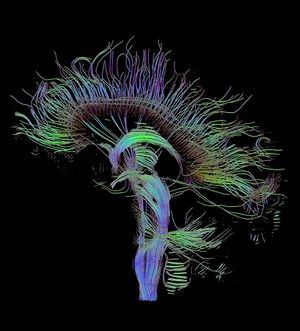

An image of neural pathways in the brain taken using diffusion tensor imaging